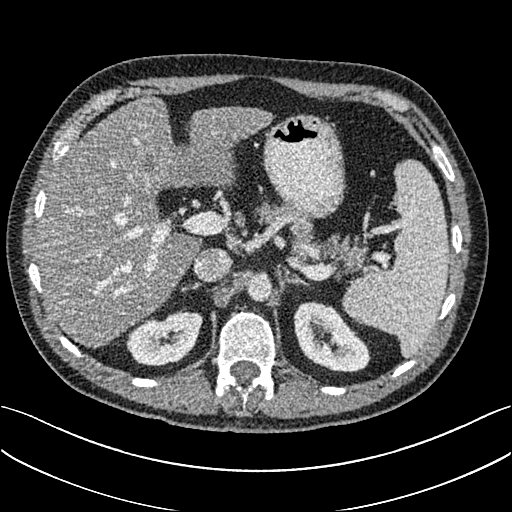

To demonstrate the effectiveness of the proposed network, we perform the qualitative comparisons over three representative abdominal images presented in Figs. 3, 5 and 7. For better evaluations of the image quality with different denoising models, zoomed regions-of-interest (ROIs) are marked by red rectangles and shown in Figs. 4, 6 and 8 respectively. Note that all results from different denoising models focus on two aspects: content restoration and noise-reduction. All CT images in axial view are displayed in the angiography window [-160, 240]HU.

The real NDCT images and corresponding LDCT images are presented in Figs. 3a and 3b. As observed, there are distinctions between ground truth (NDCT) images and LDCT images. Figs. 3a and 7a show the lesions/metastasis. Fig. 5a presents focal fatty sparing/focal fat. In Figs. 4a, 6a and 8a, these lesions can be clearly observed in NDCT images; in contrast, from Figs. 4b, 6b, and 8b, it can be seen that the original LDCT image is noisy, and lacks structural features for task-based clinical diagnosis. All adopted denoising models suppress noise to some extent.

Mean-based methods can effectively reduce noise, but the side effect is impaired image contents. In Fig. 3c, -net greatly suppresses the noise, but blurs some crucial structural information in the porta hepatis region. Meanwhile, some waxy artifacts can still be observed in Fig. 6c. -net does not produce good visual quality because it assumes that the noise is independent of local characteristics of the images. Even though it retains high SNR, its results are not clinically preferable. Compared with -net, in Figs. 3d and 5d, it can been seen that -net encourages less blurring and preserves more structural information. However, as observed in Fig. 4d, it still over-smooths some anatomical details. Meanwhile, in Fig. 6d, there are some blocky effects marked by the blue arrow. The results obtained by RED-CNN [35] deliver high SNR but blur the vessel details as shown in Figs. 4i and 6i.

For SL-based methods, as observed in Figs. 3e and 5e, SL-net generates images with higher contrast resolution and preserves texture of real NDCT images better than -net and -net. However, Figs. 4e and 6e show that SL-net does not preserve the structural features well, and there still remain small streak artifacts. Subsequently, in Figs. 4e and 4f, SL-net and MSL-net have low frequency image intensity variance because SSIM/MS-SSIM is insensitive to uniform biases [49, 51]. On the other hand, -net preserves the overall image intensity, but it does not preserve high contrast resolution well as SL-net and MSL-net do.

From Figs. 7 and 8, we can see mean-based and SL-based methods work well with effective noise suppression and artifact removal. However, the illustrations in Fig. 8 show that these methods blur the local strutural features. Our proposed SMGAN-based methods present a better edge preservation than the competing methods.

Overall, the observations above support the following statements. First, although the voxel-wise methods show good noise-reduction properties, to some extent they blur the contents and lead to the loss of structural details because they optimize the results in the voxel-wise manner. Second, SL-based methods better preserve texture than mean-based methods, but they cannot preserve overall image intensity. Third, the results produced by the proposed SMGAN-3D demonstrate the benefits of the combination of two loss functions and the importance of the adversarial training [41, 42].